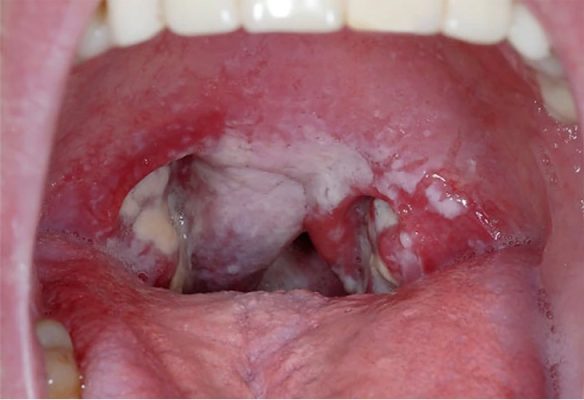

Viêm họng xuất tiết: Nguyên nhân, triệu chứng và cách điều trị

Viêm họng xuất tiết là tình trạng niêm mạc họng bị viêm, tăng tiết dịch nhầy, gây khó chịu, đau rát cổ họng, ho dai...